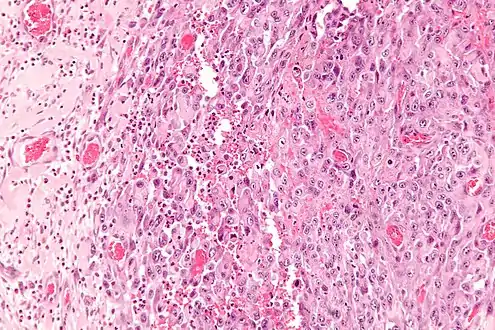

Histologically, epithelioid sarcoma forms nodules with central necrosis surrounded by bland, polygonal cells with eosinophilic cytoplasm and peripheral spindling.[3] Epithelioid sarcomas typically express vimentin, cytokeratins, epithelial membrane antigen, and CD34, whereas they are usually negative for S100, desmin, and FLI1 (FLI-1).[3] They typically stain positive for CA125.[4]

Intermed. mag.